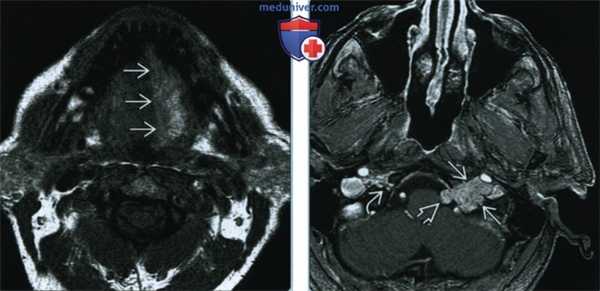

(Слева) При МРТ Т1 в аксиальной проекции наблюдается асимметрия сигнала языка. Правая половина языка не изменена; четко отграниченная левая половина языка дает патологически усиленный сигнал. Усиление сигнала свидетельствует о жировой инфильтрации и требует исследования канала подъязычного нерва.

(Справа) При МРТ Т1 с КУ в аксиальной проекции определяется дольчатое объемное образование левого подъязычного канала, распространяющееся в цистерну продолговатого мозга. Обратите внимание на отсутствие изменений правого канала подъязычного нерва. Отмечается равномерное контрастирование объемного образования, что характерно для шванномы. В ткани крупных опухолей часто наблюдаются кистозные изменения.